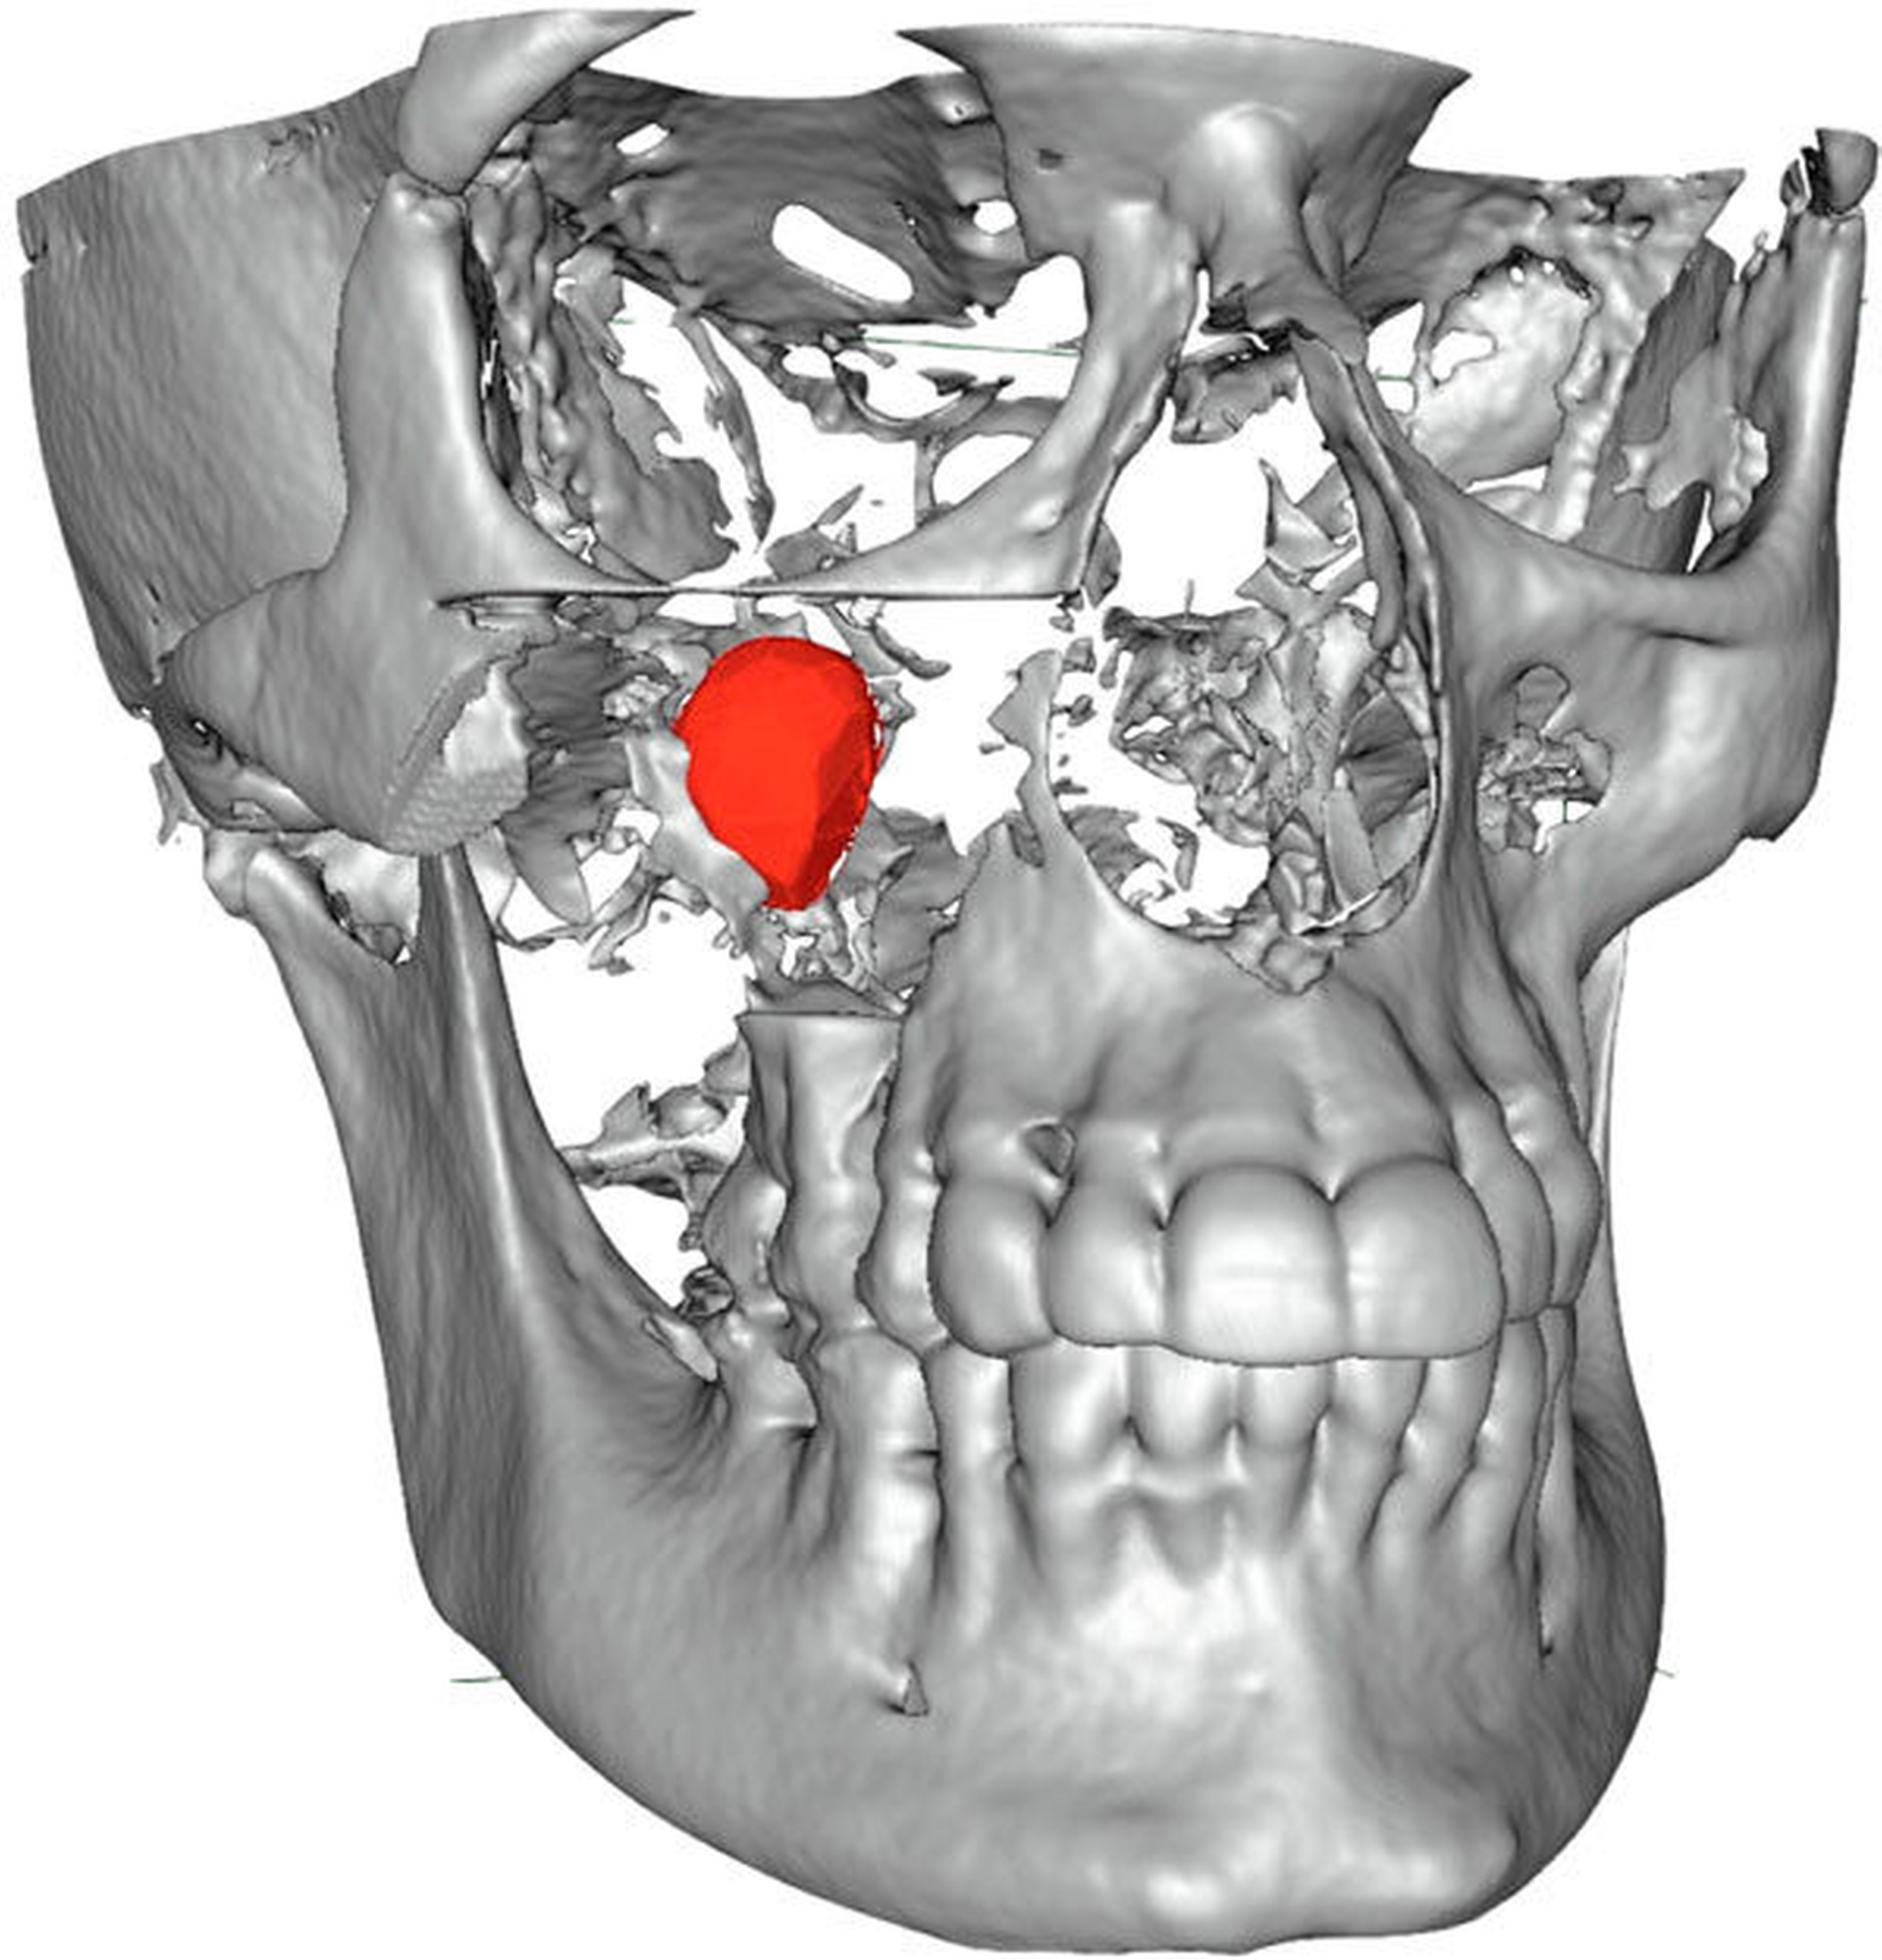

Die Durchführung einer digitalen Volumentomografie (DVT) zeigte die dreidimensionale Ausdehnung der eiförmigen Raumforderung mit einem Volumen von 2,34 cm3 (Abbildung 2).

Anfang November erfolgte in Absprache und auf Wunsch der Patientin die operative Befundentfernung im Sinne einer diagnostischen transoralen Antrozystektomie in Intubationsnarkose. Nach paramarginaler Schnittführung und maxillärer Fensterung stellte sich der oben beschriebene Befund in situ als septierte, prall-elastische Raumforderung mit rötlichem Kolorit dar (Abbildung 3a). Nach der vollständigen endoskopisch-gestützten Exstirpation (Abbildung 3b) präsentierte sich das makroskopische Präparat als bräunlich-graue, solide Masse, umgeben von einer für Zysten typischen Bindegewebskapsel (Abbildung 3c), was in Zusammenschau mit der positiven Vitalitätstestung am ehesten die Verdachtsdiagnose einer odontogenen Keratozyste unterstützte. Nach sorgfältiger Spülung der Kieferhöhle wurde der entnommene Knochendeckel unter Verwendung von zwei Miniosteosyntheseplatten belastungsstabil re-inseriert und das Weichgewebe mittels Naht verschlossen (Abbildung 3d).